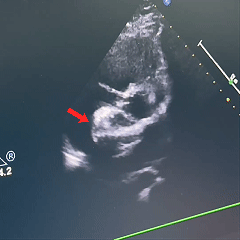

术中复测及封堵策略:术中超声复测缺损大小约19.1×17.9mm,经综合评估后,决定经股路径介入,选择BDASD-I 28可降解封堵器、16F可降解封堵器介入输送系统进行封堵,手术全程通过超声+DSA引导进行。

超声下确定封堵器左右两盘骑跨在房间隔两侧

超声下,封堵器结构稳定无散开,判断锁定成功

封堵器位置正确、夹持稳定、形态良好、无残余分流,封堵手术成功